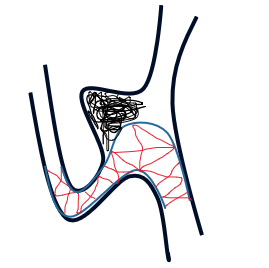

瘤颈较宽,均匀累及双侧分支,计划选择金属覆盖率高的编织型支架,单一支架缩窄瘤颈,辅助弹簧圈栓塞(如下图);

能更好保护瘤颈和重建血管,起到一定血流导向的作用,达到远期治愈目的。由于瘤颈较宽,备“T形”支架技术辅助栓塞。